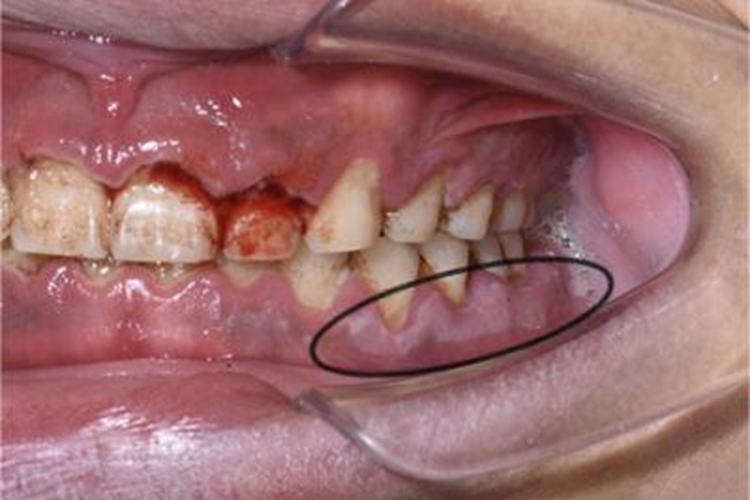

急性坏死性溃疡性龈炎发生后,检查时可见患者牙龈部位糜烂,糜烂面形状不规则,表面可有灰白色坏死物,同时还可伴有出血,患者有疼痛感。